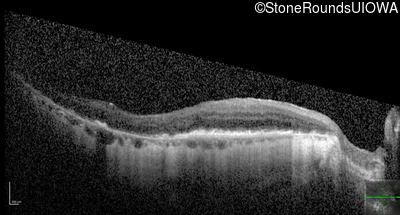

Optical Coherence Tomography - Right - 20/25 -1

Exemplar / OCT Stack

Optical Coherence Tomography - Left - 20/80 -1